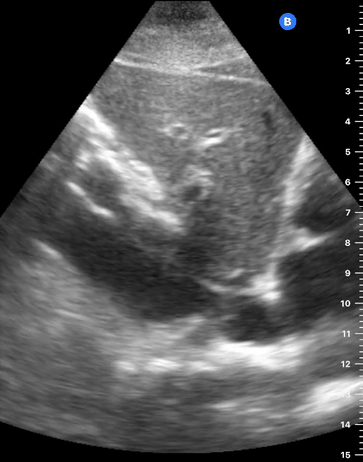

This is the standard window taught in FAST and might be the only one available during cardiopulmonary resuscitation (CPR). This view uses the liver as an acoustic window. To obtain good visualization is essential to handle the probe almost parallel to the anterior abdominal wall, trying to place it under the xiphoid process, pointing to the left shoulder. A deep inspiration or half inspiration can be useful to bring the heart closer to the probe and improve visualisation.

Remember that in the cardiac preset, the screen marking is on the right side. As a result, and unlike the FAST exam, the probe marking points towards the patient’s left. This view is used mainly to look for pericardial fluid, but it also provides information about ventricle size, chamber relationship and valvular abnormalities.